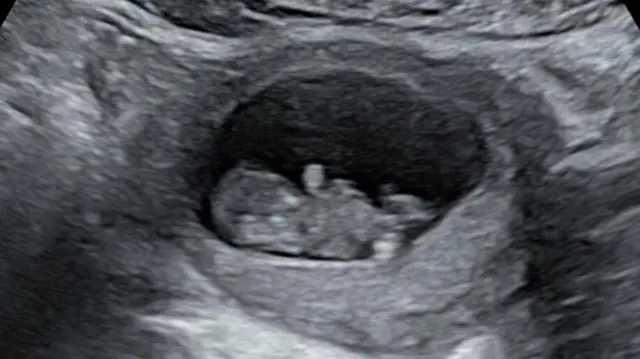

ልጁ ወንድ መሆኑን ከ20 ሳምንት በኋላ በአልትራሳውንድ ስካን አረጋገጠች። ሃድሰን ሲሉ ስም አወጡለት። ልጁ ሃይፖፕላስቲክ የተሰኘ የልብ በሽታ ነበረበት።